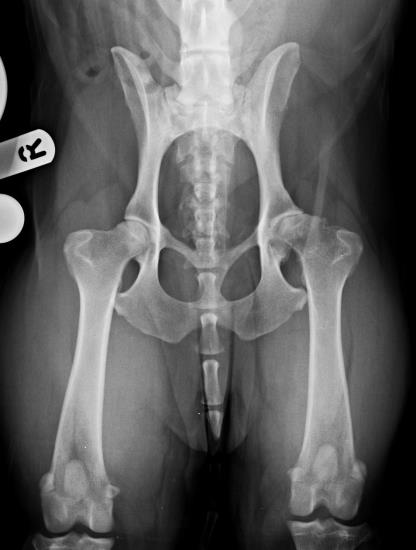

Total hip replacement at Eastcott Referrals Swindon

During the last 5 years, we have developed a well-established total hip replacement programme at Eastcott Referrals using the Biomedtrix Universal Hip system. We are able to offer this life-enhancing surgery to a wide range of patients from cats and toy dogs to giant breed dogs. Total hip replacement is an extremely effective treatment for a variety of conditions affecting the hip including hip dysplasia, osteoarthritis, failed femoral head and neck excision, complex femoral head fractures or femoral head necrosis (Legg-Calve-Perthes disease). We are always keen to see potential cases early on in the progress of disease. This allows us to discuss all the options for treatment, the expected outcomes and potential complications that could be encountered. We believe that it is important to ensure that owners are thoroughly counselled prior to embarking on surgery and will usually recommend an initial course of aggressive conservative treatment. If successful, this can allow surgery to be avoided or postponed, but will also optimise the physical condition of animals which do go on to have total hip replacement. Surgery is performed by our experienced orthopaedic team led by RCVS Recognised Specialist in Orthopaedic Surgery, Duncan Barnes. We are happy to discuss any potential cases with you prior to referral by phone or email.